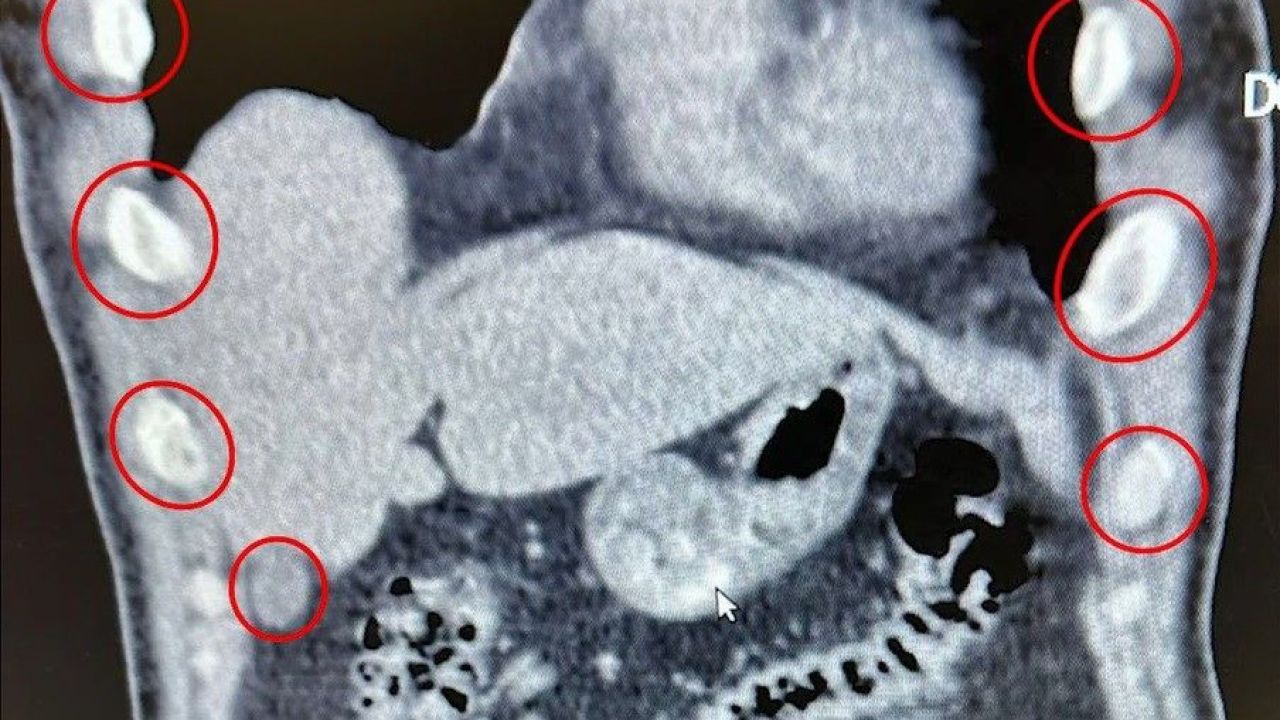

Bitlis İl Emniyet Müdürlüğü, uyuşturucu ile mücadele kapsamında gerçekleştirdiği operasyonda büyük bir sevkiyatı engelledi. Tatvan ilçesinde durdurulan bir yolcu otobüsünde seyahat eden yabancı uyruklu iki kişi, mideye gizledikleri 136 kapsül uyuşturucu maddeyle yakalandı.

1 Kilo 48 Gram Metamfetamin Tespit Edildi

Şüphelilerin sağlık kontrolleri sırasında yapılan tıbbi müdahalede, toplam 1 kilo 48 gram metamfetamin içeren 136 kapsülün yutularak taşındığı ortaya çıktı. Zanlılar, “Uyuşturucu Madde İmal ve Ticareti” suçlamasıyla gözaltına alındı. Emniyetteki işlemlerinin ardından çıkarıldıkları mahkemece tutuklanarak cezaevine gönderildi.